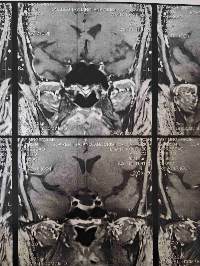

Mesmo assim ela conseguiu controlar câncer no estomago porém se espalhou tumores na coluna .

Protocolo pre-cirurgico👆